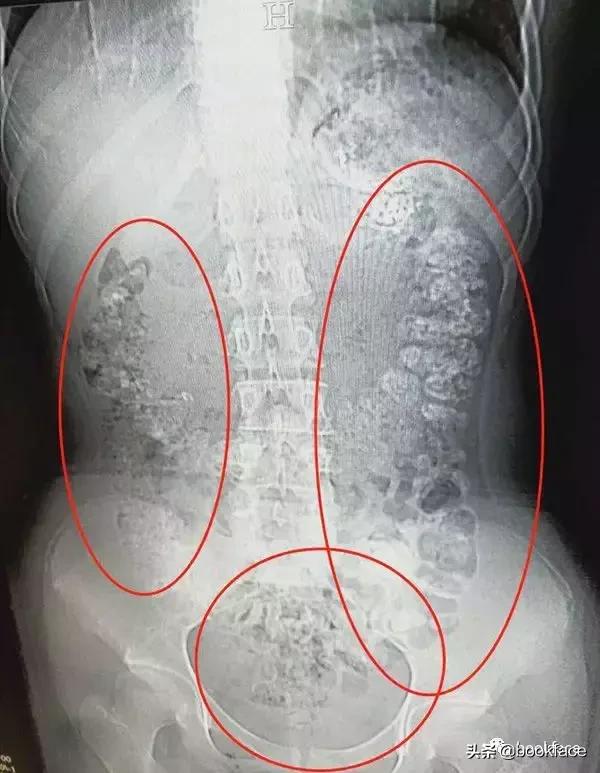

医生检查后发现,小沈胃肠道布满一颗颗圆圆的高密度阴影——没有消化的珍珠。

小女孩可能是怕父母说她,隐瞒了病史——这么多未消化的珍珠,不像喝一杯奶茶就积累的,应该是近期喝了一段时间造成的。

最后,医生给小沈开了润肠通便的药物,帮助她将未消化的珍珠排出体外。

珍珠奶茶里的珍珠是木薯淀粉制成,本身就不易消化。对于幼儿和老年人而言,胃肠功能较弱,如果进食过多的珍珠奶茶容易增加肠道堵塞的风险。